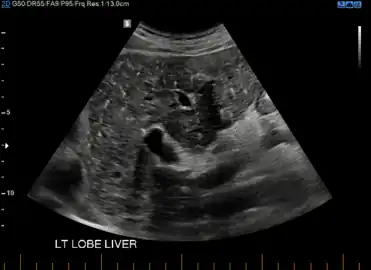

von Meyenburg Complex in ultrasound. Numerous little cysts with ringdown artefacts. -